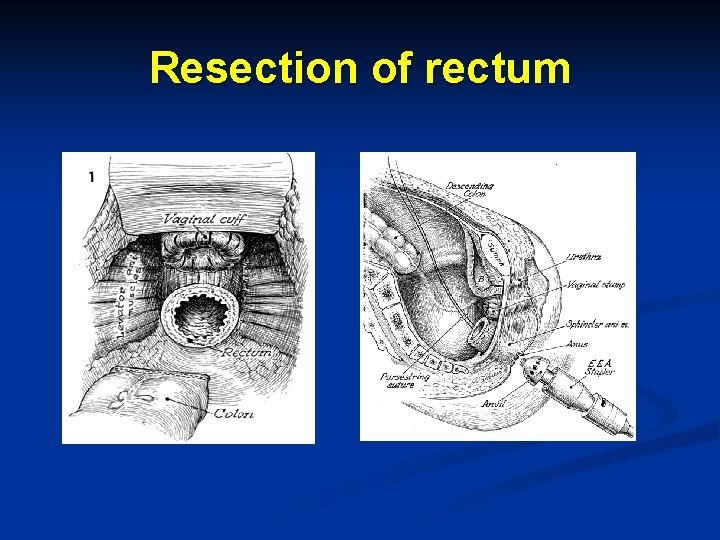

Resection of rectum